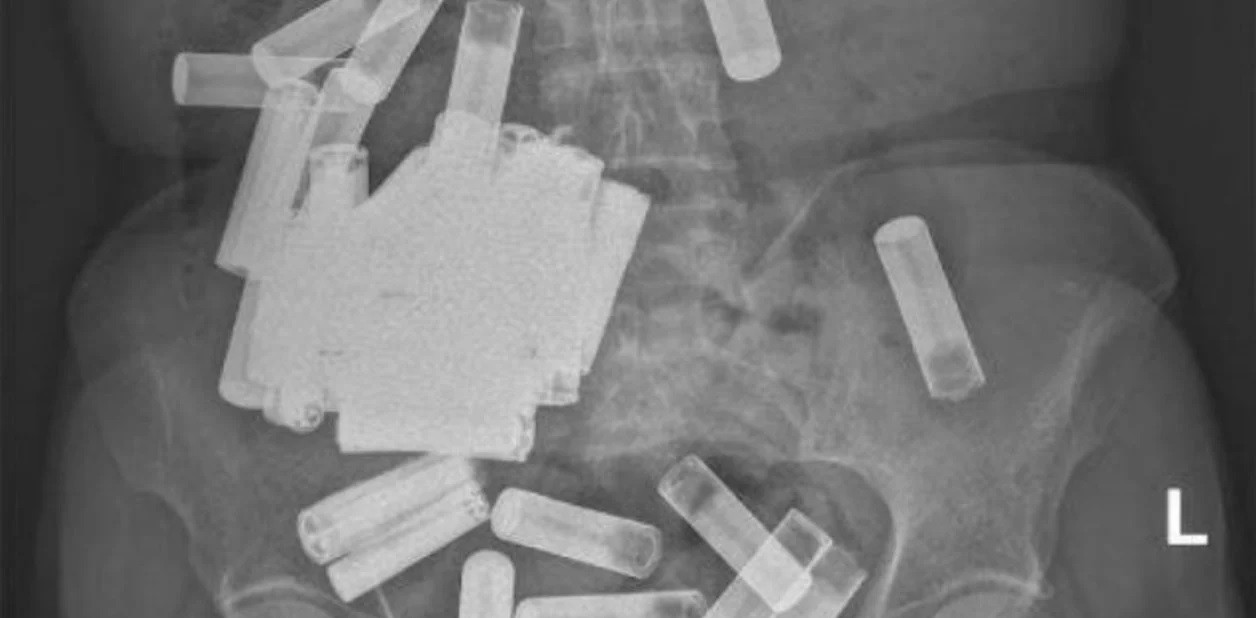

Una radiografía reveló una multitud de pilas en su abdomen, aunque afortunadamente ninguna parecía estar obstruyendo su tracto gastrointestinal (GI) y ninguna batería mostraba signos de daño estructural.

Luego, la mujer se sometió a una laparotomía, en la que los cirujanos hicieron una incisión en el estómago y extrajo 46 baterías del órgano, entre pilas AA y AAA.

Cuatro baterías adicionales, atascadas en el colon, fueron "ordeñadas" en el recto y extraídas por el ano; esto elevó el número total de baterías ingeridas a 55.

Por último, la exploración de rayos X confirmó que el tracto GI de la mujer estaba oficialmente libre de pilas y ella tuvo una "recuperación sin incidentes".